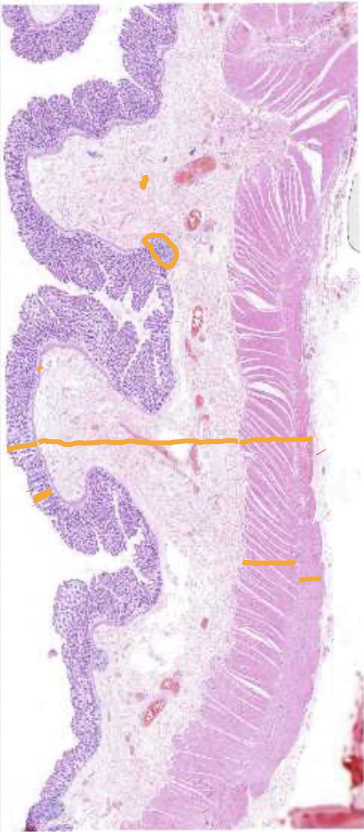

Well differentiated colon adenocarcinoma

Gland-like structures at wrong location in well differentiated colon adenocarcinoma

Well differentiated colon adenocarcinoma - Mucosa area

Well differentiated colon adenocarcinoma - Muscularis externa layers

Well differentiated colon adenocarcinoma - Submucosa area

Different sized, closely bound gland-like tubule/crypts

Cell debris in the lumen of the glands (necrotic cell remains mixed with inflammatory cells ) - can be a sign of relative lability of the cancer cells and/or be caused by ischaemia

No lamina propria between, located very close to each other - Pushed together, not growing in a normal way

Why is all of these images diagnosed as well differentiated colon adenocarcinoma and not poorly differentiated?

Even though there are cancer cells present that are morphologically different from normal, they are still forming some kind of tubular structure (not the normal shape, but still there) → Well differentiated

Morphology gives us an indication of the likely behaviour of this cancer

Good sign, but unfortunately it has spread through the intestinal wall